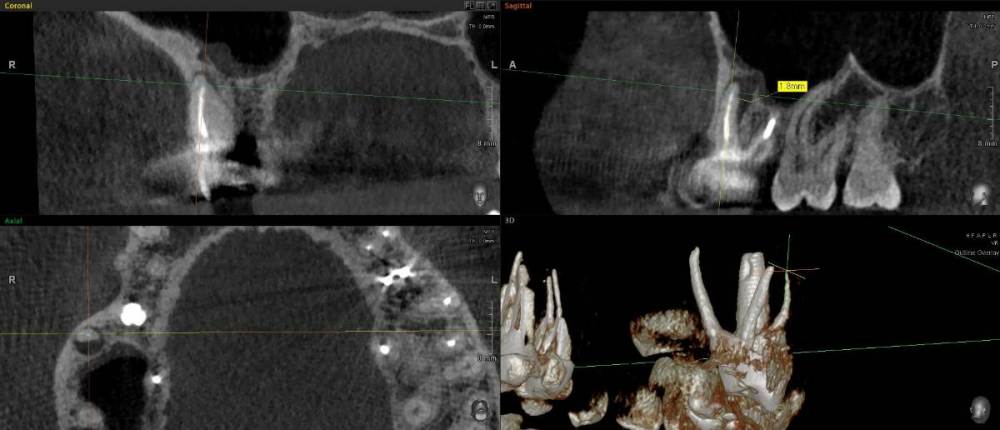

ict Опубликовано 27 мая, 2022 Автор Поделиться Опубликовано 27 мая, 2022 для истории. Через полгода появился свищ у проблемного канала. Перед резекцией верхушки корня хирург попросил перепломбировать канал. думаю перепломбировать не было смысла до конца все равно 0.9мм не смогли пройти, но и вреда не было - верхушка спиливалась, пломбу высверлили в центре и пломба полностью не снималась. Думаю верхушка с канальцами и сгнила. На КТ (справа внизу) при выборе отображения плотности видно, что у верхушки на 1.7мм есть ступенька с меньшей твердостью (декальцинирован) Ссылка на комментарий